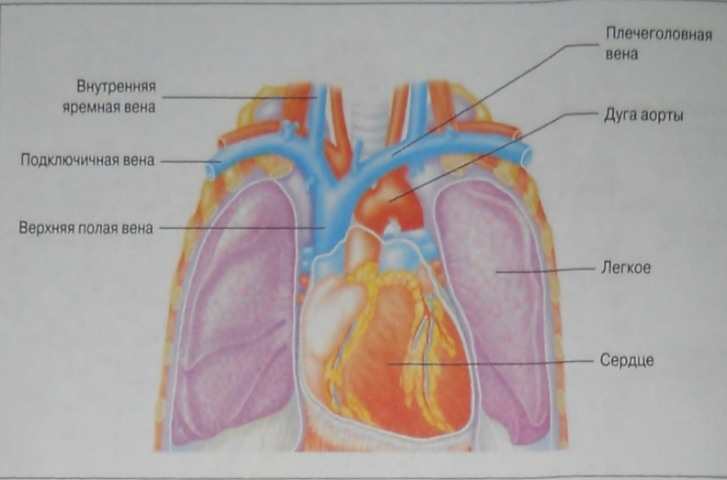

Анатомия внутренней яремной вены: КТ изображения